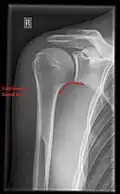

Fracture

Fractures of shoulder bones can include clavicular fractures, scapular fractures, and fractures of the upper humerus.

Conventional x-rays and ultrasonography are the primary tools used to confirm a diagnosis of injuries sustained to the rotator cuff. For extended clinical questions, imaging through Magnetic Resonance with or without intraarticular contrast agent is indicated.

Hodler et al. recommend starting scanning with conventional x-rays taken from at least two planes, since this method gives a wide first impression and even has the chance of exposing any frequent shoulder pathologies, i.e., decompensated rotator cuff tears, tendinitis calcarea, dislocations, fractures, usures, and/or osteophytes. Furthermore, x-rays are required for the planning of an optimal CT or MR image.[25]

X-ray

Projectional radiography views of the shoulder include:

AP-projection 40° posterior oblique after Grashey

The body has to be rotated about 30 to 45 degrees towards the shoulder to be imaged, and the standing or sitting patient lets the arm hang. This method reveals the joint gap and the vertical alignment towards the socket.[26]